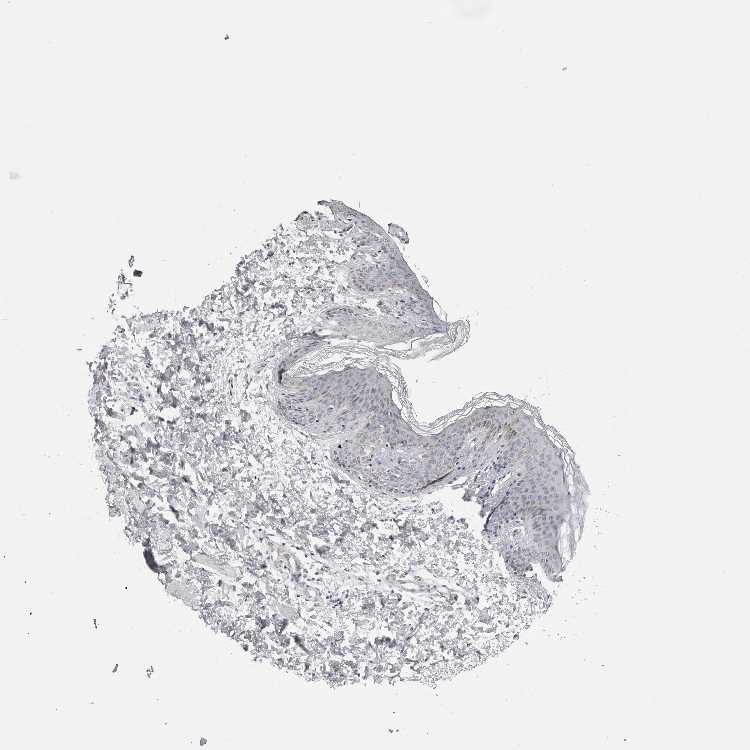

SKIN 1 - Antibody stainingi

Antibody staining in the annotated cell types in the current human tissue is reported as not detected, low, medium, or high, based on conventional immunohistochemistry profiling in selected tissues. This score is based on the combination of the staining intensity and fraction of stained cells.

Each image is clickable and will lead to virtual microscopy that enables deeper exploration of all samples and also displays staining intensity scores, fraction scores and subcellular localization as well as patient and tissue information for each sample.

Antibody HPA028494

Langerhans Not detected

Fibroblasts Not detected

Keratinocytes Low

Melanocytes Not detected